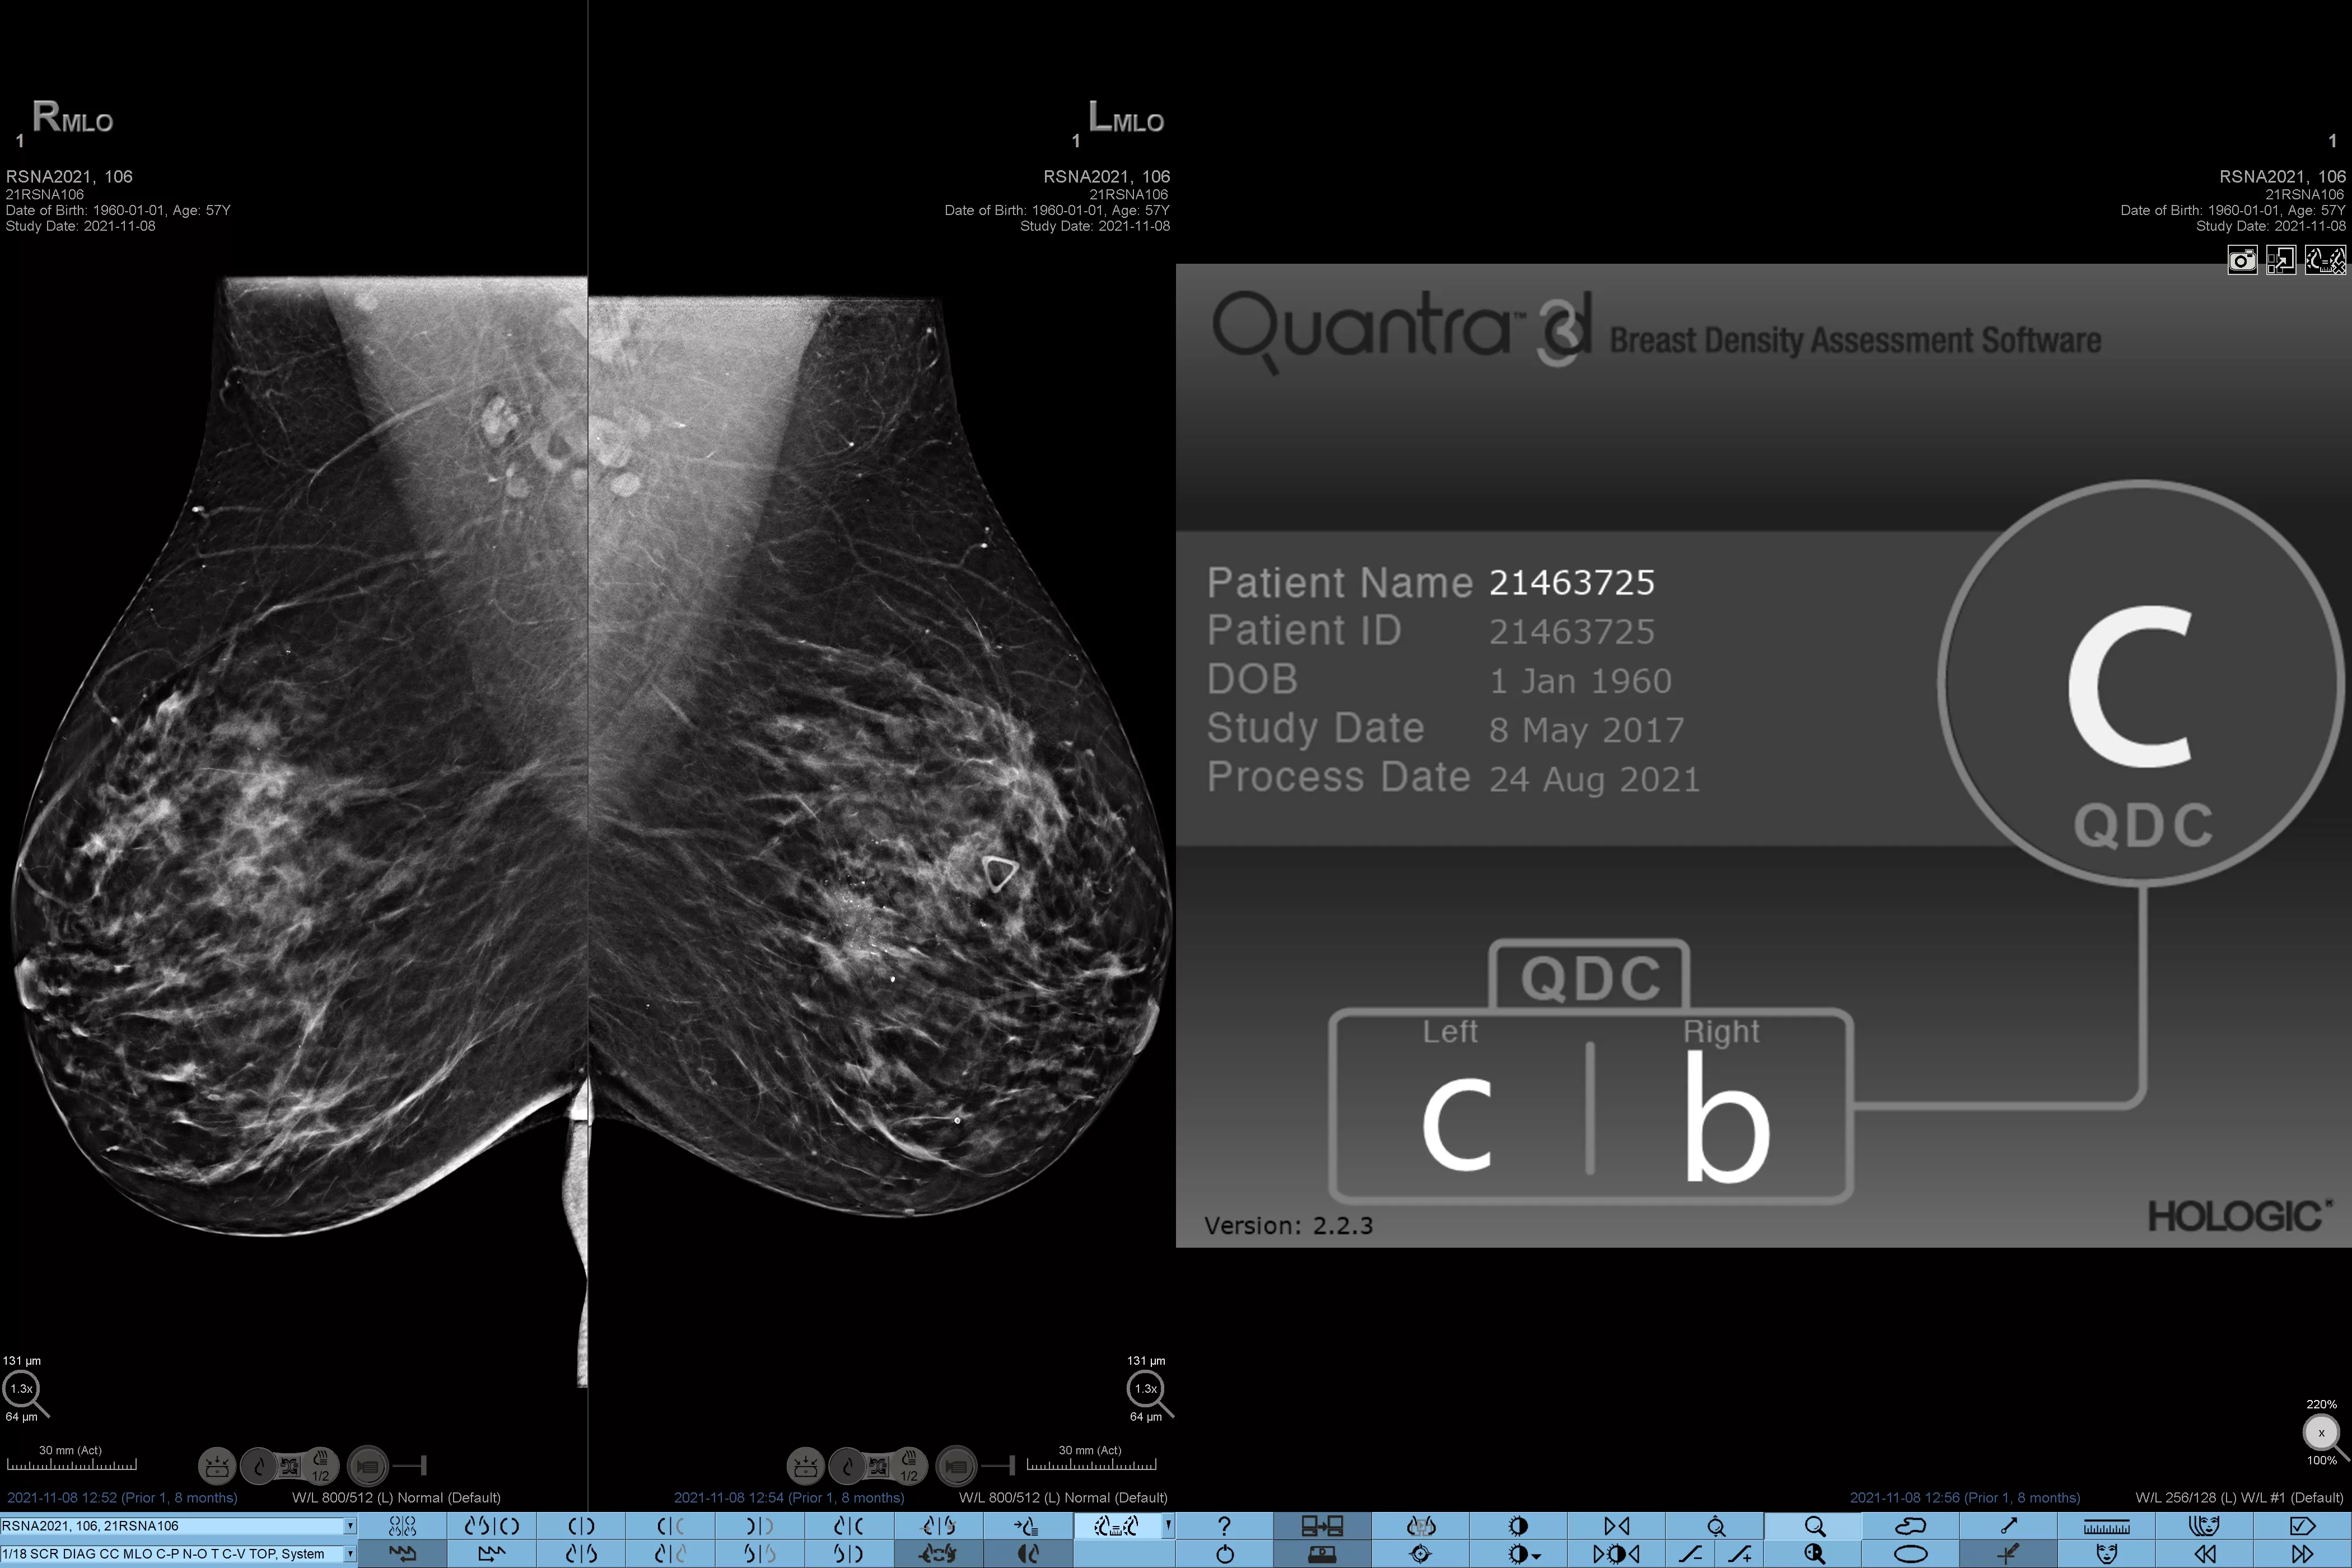

Higher breast density is known to increase a woman’s risk for breast cancer.1 The need for accurate, unbiased analysis is therefore critical. Powered by machine learning, Quantra technology software analyses both 2D™ and tomosynthesis images for distribution and texture of parenchymal tissue. It categorises breasts in four breast composition categories consistent with guidance from the American College of Radiology (ACR) BI-RADS Atlas 5th Edition.2

8. Breast composition categories as described in ACR BI-RADS Atlas.